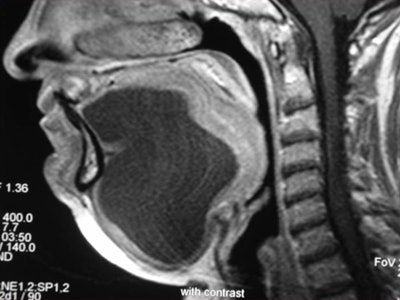

At today's session, Dr. Alexandra Borges, from the Portuguese Institute of Oncology in Lisbon, will present on the anatomy and imaging techniques relevant to pathologies of the oral cavity and salivary glands. She will provide useful tips regarding the choice and tailoring of imaging technique, and will review relevant anatomic relationships underlying the most common patterns of disease spread.

But to image this region of the body productively, radiologists need to be familiar with the intricate anatomy of the oral cavity, recognize the most common routes of disease spread, tailor imaging studies to specific clinical presentations, and issue meaningful reports answering pertinent clinical questions.

"Imaging may be the only way to assess clinically occult lesions such as the retromolar trigone in patients with trismus and the deep lobe of the parotid gland, therefore having a major impact on their management," she pointed out.

CT and MR are currently the primary imaging modalities to assess the oral cavity. CT is preferred in patients presenting with infectious/inflammatory syndrome. According to Borges, in patients presenting with oral cavity cancer, the use of dental CT software with the acquisition of para-axial and parasagittal high-resolution images in bone algorithm is most valuable in depicting early cortical bone erosion. MRI provides better soft-tissue resolution, and is the first choice in evaluating the deep extent of tumors and for the management of patients presenting with submucosal lesions.

Referring to the choice of imaging technique, she highlights the importance of considering different patients' specificities. Heavy smokers and drinkers prone to salivary stasis, difficulty in swallowing, and dyspnea are not good candidates for MRI, as this technique is very prone to motion artifacts, and patients with many dental fillings and/or dental implants may do better with MRI than with CT, she explained.

Finally, she emphasized that when using MRI, it is crucial to instruct a patient not to swallow and to breathe quietly during the entire examination. The use of surface coils can be very helpful for the imaging of superficially located lesions such as the parotid and submandibular glands and the floor of the mouth.